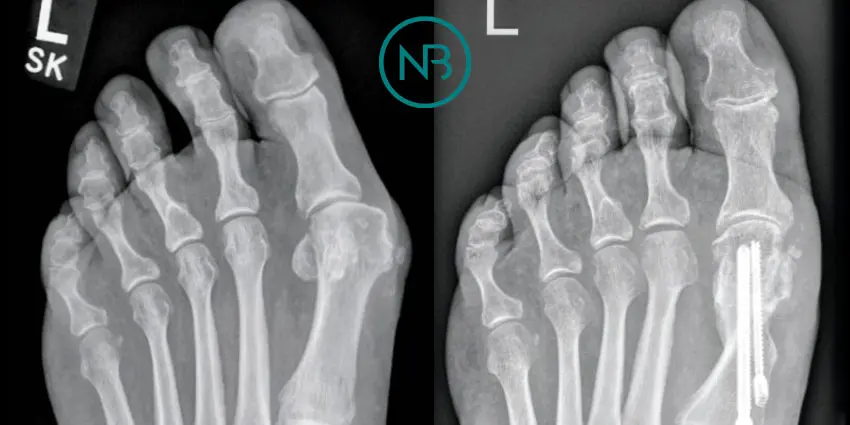

Bunion (Hallux Valgus) - Minimally Invasive Surgical Correction

More than one third of people over the age of 65 have bunions. It affects ladies twice as much as men. Many people live with this condition without any trouble. For many others however this stubborn lump on the inner side of the foot creates significant problem when shoes become more and more difficult to ware, and the big to continues to progressively drift laterally causing lesser toes deformities, forming painful callosities and drastically reducing quality of life. For these patients a corrective surgery is the only reliable option.

I correct bunions through minimally invasive surgery. It means cutting and resetting bones in the foot through tiny skin incisions using special instruments and implants. With minimal soft tissue trauma, and swelling this technique dramatically reduces pain and speeds up the recovery.

Bunion also called Hallux Valgus is a condition where the big toe over time gradually deviates outwards. This may lead to prominent bony bump with persistent throbbing pain over the inner side of the foot as well as great difficulty wearing shoes. Also, the big toe can encroach on neighbouring 2nd toe and make it to go either over or under it with crowding of other lesser toes. Typically, the condition progresses gradually sometimes making it nearly impossible to wear normal shoes.

Although occasionally splints helping to realign the big toe better can alleviate the discomfort to some extent, as a rule this condition is likely to progress, and the surgical correction is required to sort out the problem.